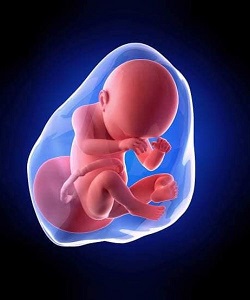

গর্ভাবস্থায় ফান্ডাল প্ল্যাসেন্টা: একটি নিরাপদ ও সাধারণ অবস্থান

পোস্টেরিয়র প্লাসেন্টা: গর্ভাবস্থায় সাধারণ ও নিরাপদ অবস্থান